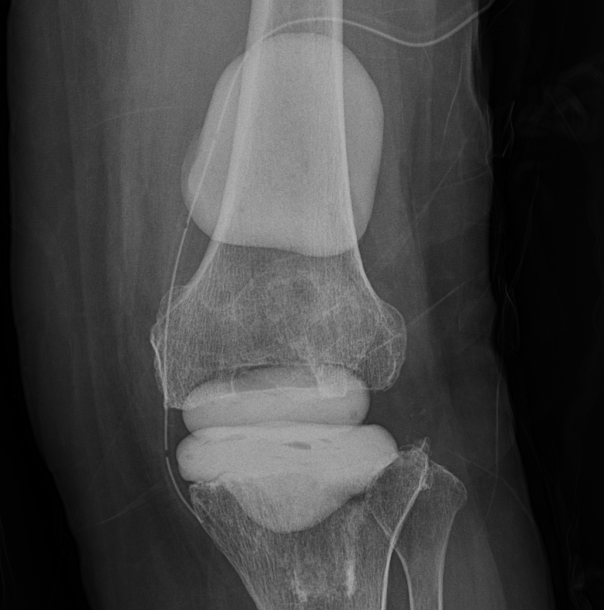

Prostalac은 감염된 인공관절을 제거한 뒤 감염을 치료하면서 환자가 일정 부분 관절을 사용할 수 있도록 항생제 방출하며 감염 치료를 돕는 항생제 함유 관절스페이서를 뜻함.

2)통상적으로 2단계 인공관절 재치환술 시행 시 사용